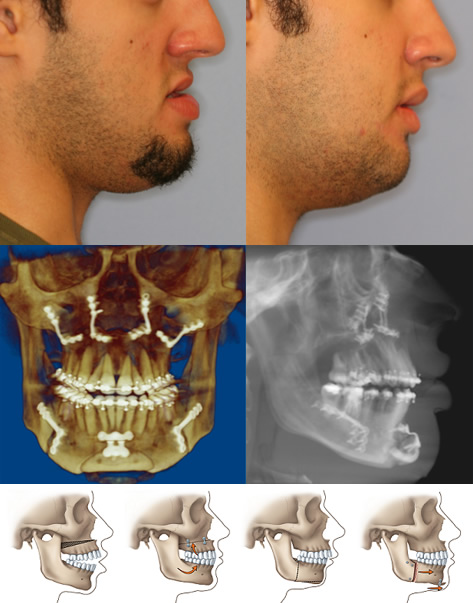

Corrective jaw surgery may reposition all or part of the upper jaw, lower jaw and chin. When you are fully informed about your case and your treatment options, you and your dental team will determine the course of treatment that is best for you.